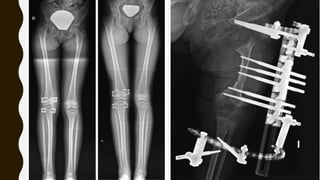

OSTEOTOMIA ALTA DE TIBIA

• Metodo de elección

• Corregir: varo, antecurvatum y RI

• Tasa de recurrencia baja si se realiza

antes de los 4 años

>10

AÑOS

TRATAMIENTO

QUIRURGICO